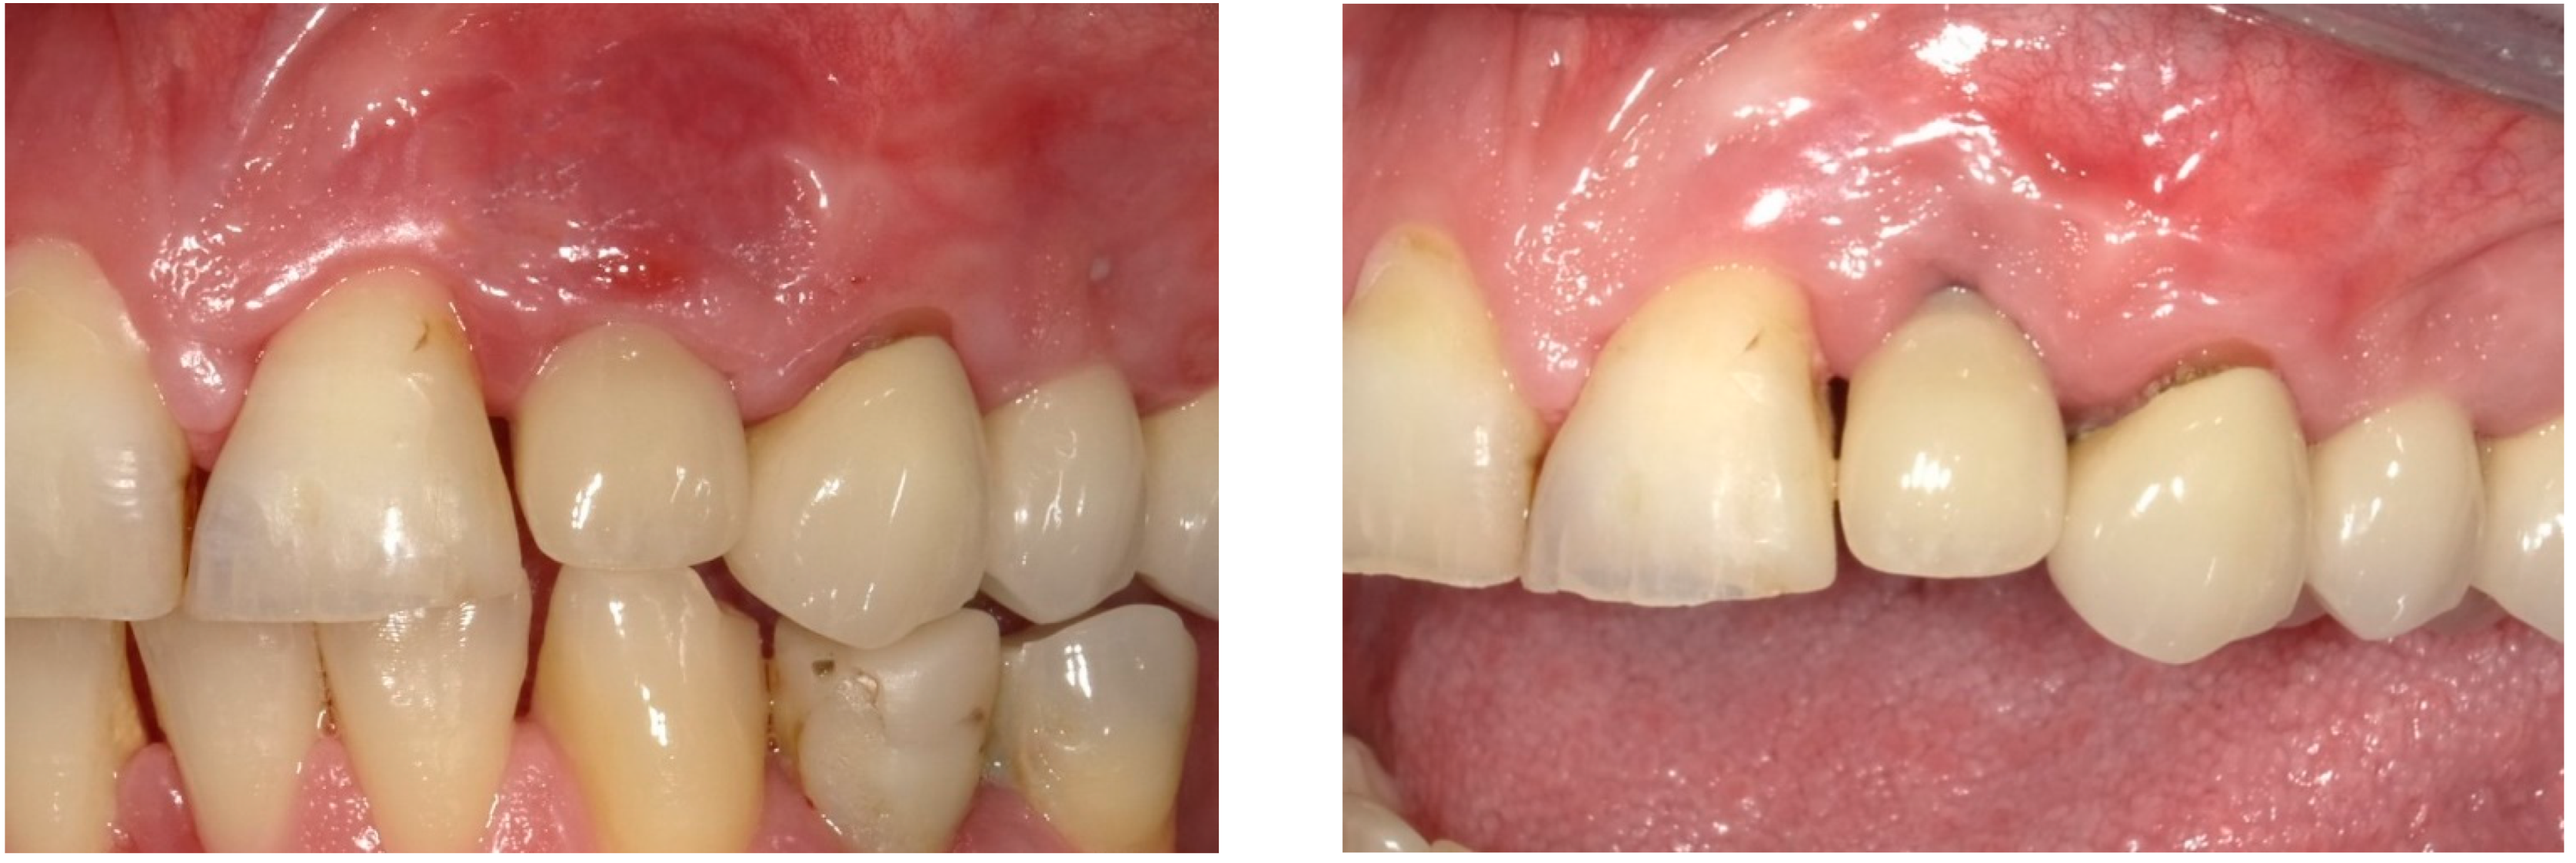

| Midfacial mucosa level at Tpre (mm) | 3.0 | 2.0 | 5.0 |

| Midfacial mucosa level at T9 (mm) | 5.0 | 6.0 | 6.0 |

| Midfacial mucosa level at T12 (mm) | 5.0 | 6.0 | 6.0 |

| Midfacial keratinized tissue width at Tpre (mm) | 3.0 | 7.0 | 5.0 |

| Midfacial keratinized tissue width at T9 (mm) | 3.0 | 3.0 | 3.0 |

| Midfacial keratinized tissue width at T12 (mm) | 3.0 | 3.0 | 2.0 |

| Mesial papilla | 1 | 1 | 0 | 0 | 2 | 2 |

| Distal papilla | 1 | 1 | 0 | 0 | 2 | 1 |

| Curvature of the facial mucosa | 1 | 1 | 2 | 2 | 1 | 2 |

| Level of the facial mucosa | 0 | 2 | 2 | 1 | 1 | 2 |

| Root convexity/soft tissue color and texture | 0 | 1 | 2 | 2 | 0 | 1 |

| Total | 3 | 6 | 6 | 5 | 6 | 8 |